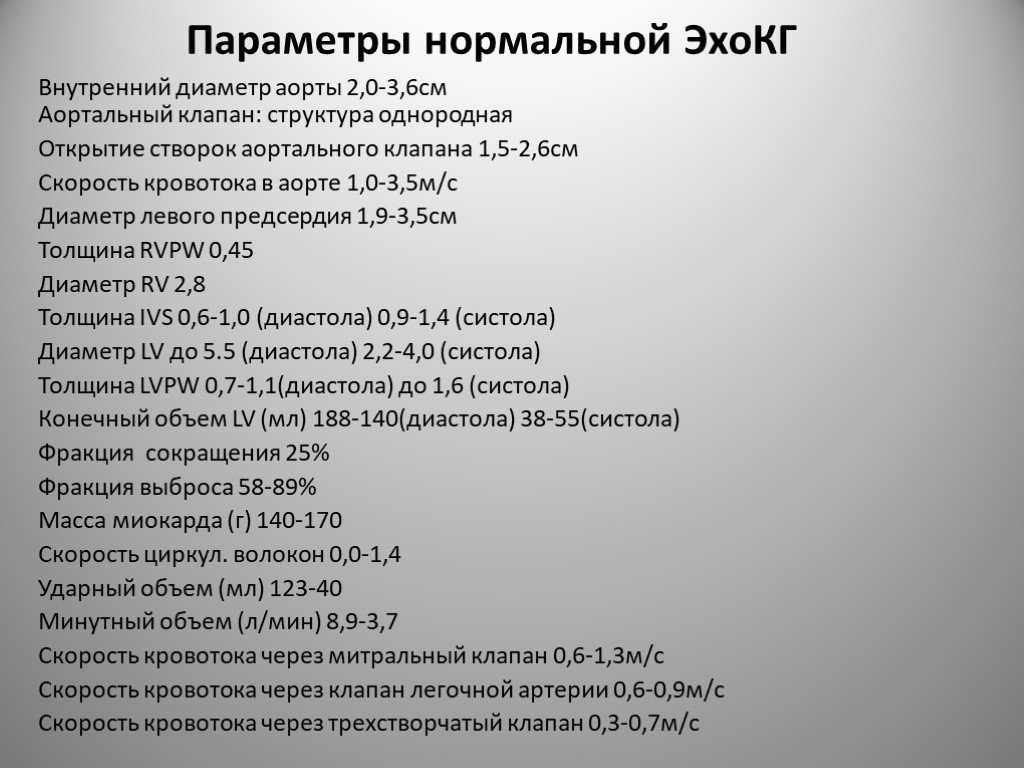

Нормальный диаметр корня аорты: медицинские нормы и отклонения